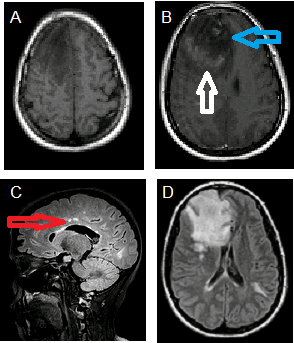

This is a patient with tumefactive MS. Notice the incomplete rim enhancement around the right frontal mass on the T1 post contrast sequence. This incomplete rim enhancement is classic for a tumefactive demyelinating lesion as opposed to a neoplasm. A. T1 precontrast and B. postcontrast images demonstrate a T1 hypointense right frontal mass with incomplete rim enhancement (white arrow) and right to left subfalcine herniation (blue arrow). C. Sagittal and D. axial FLAIR images demonstrate hyperintense lesions involving the pericallosum (red arrow) and left temporal subcortical white matter.

Given their overlapping features it is often hard to distinguish tumefactive MS from tumor although specific imaging findings favor MS. One important finding is the presence of incomplete rim enhancement. Tumors typically manifest complete rim enhancement. Other less specific findings favoring tumefactive MS include T2 isointensity in the region of enhancement, size out of proportion to vasogenic edema and secondary signs of MS such as pericallosal lesions